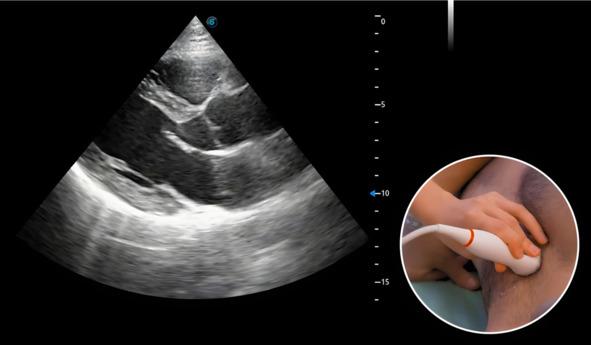

После того как пациент занял исходное положение (на левом боку, левая рука под головой, правая вдоль туловища), необходимо нанести гель на датчик и приложить к груди обследуемого. Ориентироваться следует на третье-четвертое межреберье, маркер датчика обращен на правое плечо пациента. На рис.1 можно увидеть расположение датчика на теле пациента и идеальную картинку в этой позиции.

Рис.1